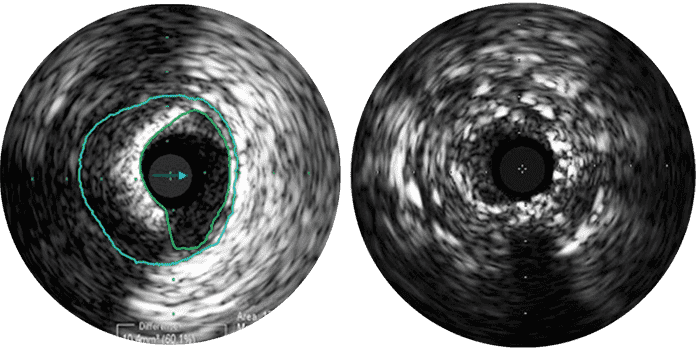

L’échographie intravasculaire (IVUS) est une technologie d’imagerie par cathéter permettant aux médecins de visualiser les vaisseaux malades depuis l’intérieur de l’artère. L’échographie intravasculaire fournit des mesures détaillées et précises de la taille de la lumière et des vaisseaux, de la surface et du volume de la plaque et de l’emplacement de repères anatomiques clés.

Une sonde d’échographie émet des ondes sonores haute-fréquence qui sont réfléchies par les parois vasculaires et renvoyées au système avec une intensité qui varie selon le tissu. L’électronique du système traite le signal pour afficher une image transversale.

L’échographie intravasculaire sert à optimiser l’implantation en vous permettant d’observer :

L’échographie intravasculaire aide à déterminer :